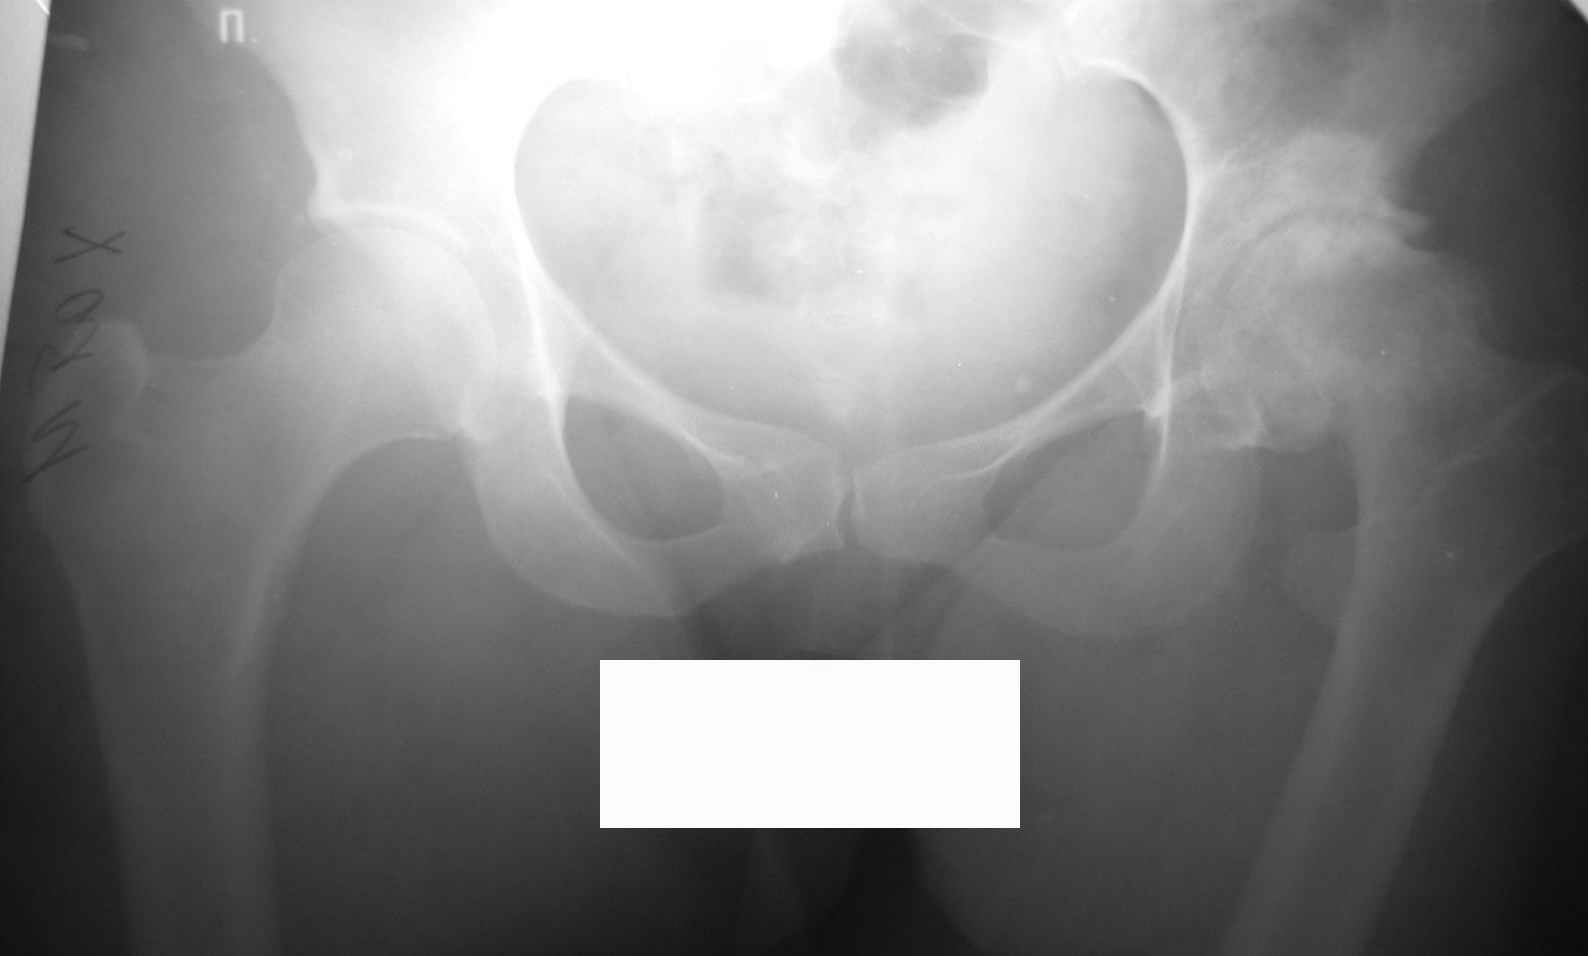

Уважаемые коллеги, во вложении р-граммы 24-летней женщины. Обратилась первично.

Жалобы на боли, ограничение движений, хромоту. Болеет с 14 лет. С её слов, перенесла болезнь Пертеса. Документов нет. Обьективно: выраженнаяприводяще-сгибательная-ротационная контрактура, функциональное укорочение - 5см.Вопросы:-какая система, на ваш взгляд, наиболее оптимальна для протезтрования?-возможно-ли выполнить протезирование в один этап,восстановив длину и функцию конечности?Спасибо.Ринат. г.Уфа

Судя по седловидной деформации головки бедренной кости можно предположить, что больная перенесла болезнь Пертеса.

Извините, Анатолий, головка не выглядит потерянной, укорочение 5 см из-за порочного положения. Подход у молодой женщины я бы выбрал в зависимости от мобильности сустава.

На ригидном суставе межвертельная остеотомия для женщины мало привлекательна, но при гипомобильности, а тем более мобильности сустава вполне пригодна. И эффект от операции мы наблюдаем больше 10 лет и для последующего эндопротезирования трудности не велики, если остеотомию правильно спланировать и выполнить (проксимальный отдел бедра после остеотомии должен соответствовать нормальной анатомической геометрии). Привожу, что под рукой - Ртг 1997 ( даме 27 лет) и 2004 года. А моделей эндопротезов бесцементной фиксации для такой рентгеноантомической формы коксартроза действительно достаточно.

По представленным раздельным Рг граммам сложно судить о причине столь значительного укорочения, вполне вероятно что причина комплексная:

1 разрушение головки

2 разрушение впадины

3 поясничный сколиоз

При предоперационном планировании дифференцируют относительное укорочение (обусловлено перекосом таза, поясничным сколиозом) конечности и абсолютное - истинное (разрушение головки бедра и вертлужной впадины, приводящее к смещению центра ротации). В идеальных условиях целью эндопротезирования является восстановление уровня центра ротации. Приводящие контрактуры, поясничный сколиоз обычно вторичны деструктивным процессам в суставе и на уровень центра ротации, абсолютное укорочение конечности не влияют.

Поэтому и важно иметь правильно выполненную Рг таза целиком, а не из половинок и с помощью референс линий определить истинное укорочение и необходимую величину коррекции. После эндопротезирования сустава решается вопрос о необходимости аддукторотомии.

По моему мнению, у Вашей пациентки выявлены последствия эпифизеолаза (slipped capital femoral epiphysis).В данный момент у нее наблюдаются признаки коксита (laminar coxitis), что является наиболее тяжелым осложнением в таких случаях. Я не мог бы предложить другого метода лечения, кроме эндопротезирования сустава. Удлиннить бедро на 5 см. можно во время операции без особых затруднений с помощью тенотомий.

Учитывая молодой возраст женщины,аналогично менению глубокоуважемного В.П. Волошина, считаю оптимальным выполнить межвертельную корригирующую остеотомию бедра с небольшой медиализацией, тенотомией сгибателей и приводящих мышц бедра. Устранение порочного приведения, сгибания и ротации на остотомии позволит выровнять длину ног, так как здесь ортопедическое укорочение за счет фиксированного приведения и сгибания бедра. Фиксацию фрагментов можно выполнить аппаратом Илизарова, что позволит обойтись без иссечения костного клина и в полеоперационном периоде будет возморжна остаточная коррекция, если что-то не удалось на операционном столе. Эффект от корригирующих медиализирующих остеотомий (уменьшение и ликвидация болевого синдрома, увеличение движений в сустве)по нашему опыту составляет от 7 до 10 лет, что позволяет отсрочить выполнение эндопротезирования. Система для имплантации, действительно, может быть любая, выбор большой, но, на наш взгляд, предпочтительна бесцементная.